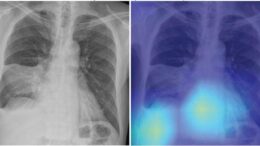

According to an accepted manuscript published in the American Roentgen Ray Society’s American Journal of Roentgenology (AJR), a deep learning-based model using initial chest radiographs predicted 30-day mortality in patients…